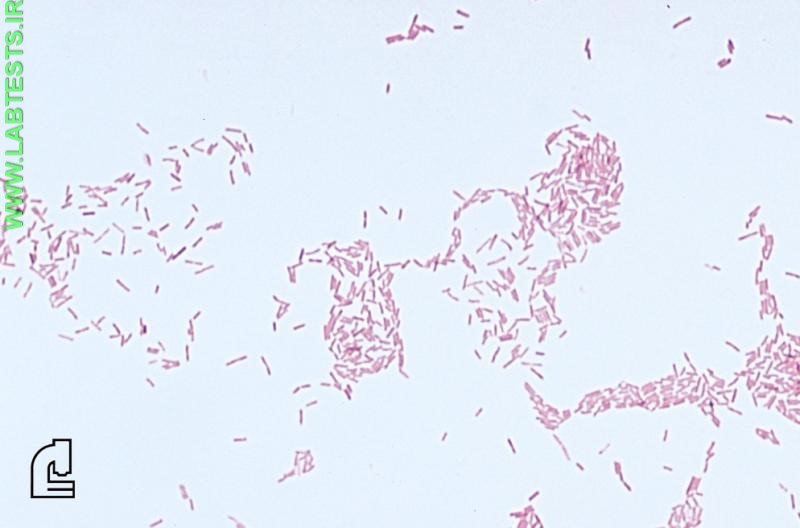

A Gram stain is used, along with a culture of the material from an infected site, to identify the cause of a bacterial infection. The Gram stain provides preliminary results on whether bacteria are present and the general type, such as the shape and whether they are Gram-positive or Gram-negative.

- Whether the bacteria are Gram-positive (purple) or Gram-negative (pink)

- Shape — round (cocci) or rods (bacilli)

- Gram-positive bacilli—Bacillus anthracis (anthrax) can cause skin infections or pneumonia (also a bioterrorism agent); Listeria monocytogenes can cause foodborne illnesses.

- Gram-negative bacilli—Escherichia coli is a common cause of urinary tract infections.

The Gram stain involves applying a sample from an infected area or a sample of bacteria grown in culture onto a glass slide. The slide is then treated with a special stain and examined under a microscope by a trained laboratorian. The color and shape of the bacteria help classify which general types of bacteria are present.